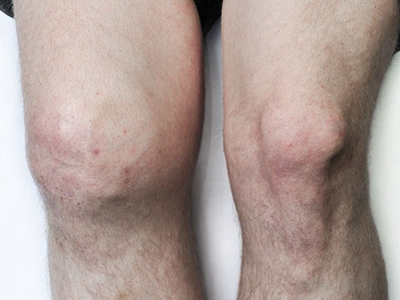

膝关节骨质增生症状图片

4、关节反复肿胀:积液多于不严重的外伤或轻度扭伤后引起关节肿胀积液,疼痛,关节周围压痛,膝关节肌肉痉挛。休息1-2个月后症状可自然消退,可以很长时间没有症状,但可因轻微外伤而反复发作,由于股四头肌无力或因疼痛,膝关节可出现“闪失”现象。

5、关节畸形:病情逐步发展,膝关节出现内翻或外翻畸形,关节骨缘增大。关节主动及被动活动范围逐步减小,关节疼痛转重,在走平路及站立时也引起疼痛感。关节韧带松弛出现关节不稳感,有些病人不能完全伸直膝关节,严重者则膝关节呈屈曲挛缩畸形。开始活动时疼痛加重,休息后缓解,以后可变为持续性疼痛。